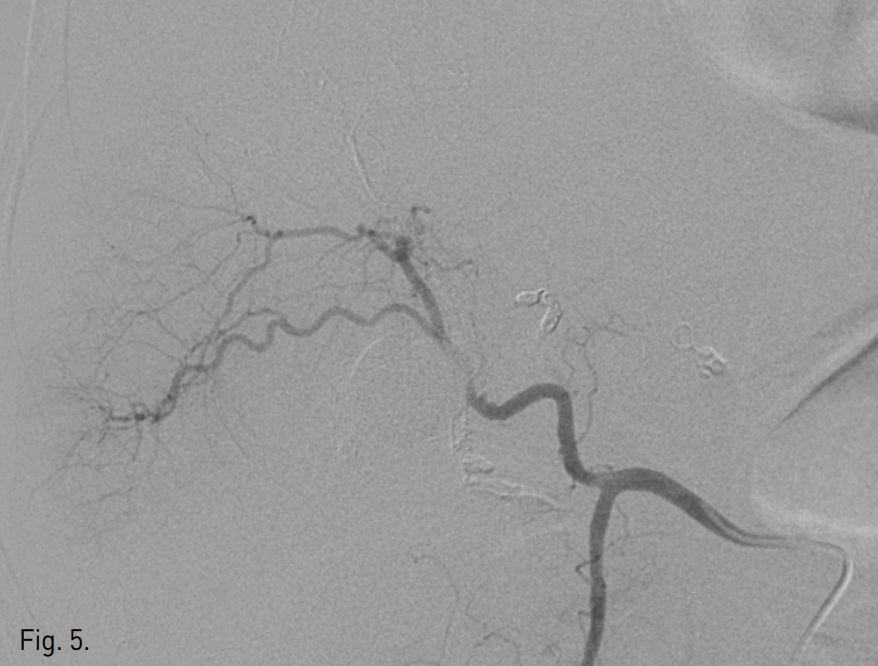

5F sheath를 우측 총대퇴동맥 내로 삽입한 후, 0.035 inch guide wire(Terumo, Tokyo, Japan)와 RH catheter(Cook, Bloomington, IN, USA)를 이용하여 총간동맥 혈관조영술을 시행함. 제 4 간분절로 가는 간동맥에서 기시하는 가성동맥류를 확인하고 0.014 inch Transcend guide wire(Boston scientific, Natick, MA, USA)와 2.2F Progreat microcatheter (Terumo, Tokyo, Japan)를 이용하여 superselection하여 4개의 tornado microcoil(Cook, Bloomington, IN, USA)과 gelatin sponge particle(gelfoa m)로 색전술을 시행함. 그러나 시술 후 시행한 혈관촬영술에서 처음에는 보이지 않던 간내 곁순환에 의해서 가성동맥류는 여전히 관찰됨(Fig. 3). 초음파 유도 하에 22G Chiba needle(A&A medical, Seoul, Korea)로 가성동맥류를 직접 천자하여 Yellow sheath(A&A medical, Seoul, Korea)를 삽입하고 1% sodium tetradecyl sulfate (Tromboject) 2 cc, N-butyl-2-cyanoacrylate(glue)(B. Braun, Melsungen AG, Germany)와 리피오돌 1:4 혼합액 4 cc로 색전술을 시행함(Fig. 4). 이 과정에서 우측 간동맥 전분절 분지내로 혼합액의 일부가 유입되었음. 다시 시행한 혈관 조영술에서 가성동맥류가 완전히 폐색된 것을 확인함 (Fig. 5).

Fig. 5

Common hepatic angiography after the embolization shows no opacification in the pseudoaneurysm.